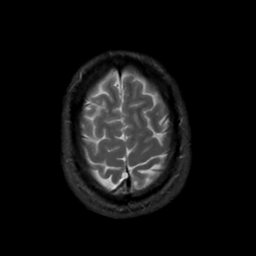

MR Study #3, February 24, 1991 -- Slice #43

[Home][Help][Clinical][Tour 1][Tour 2] Slice 43